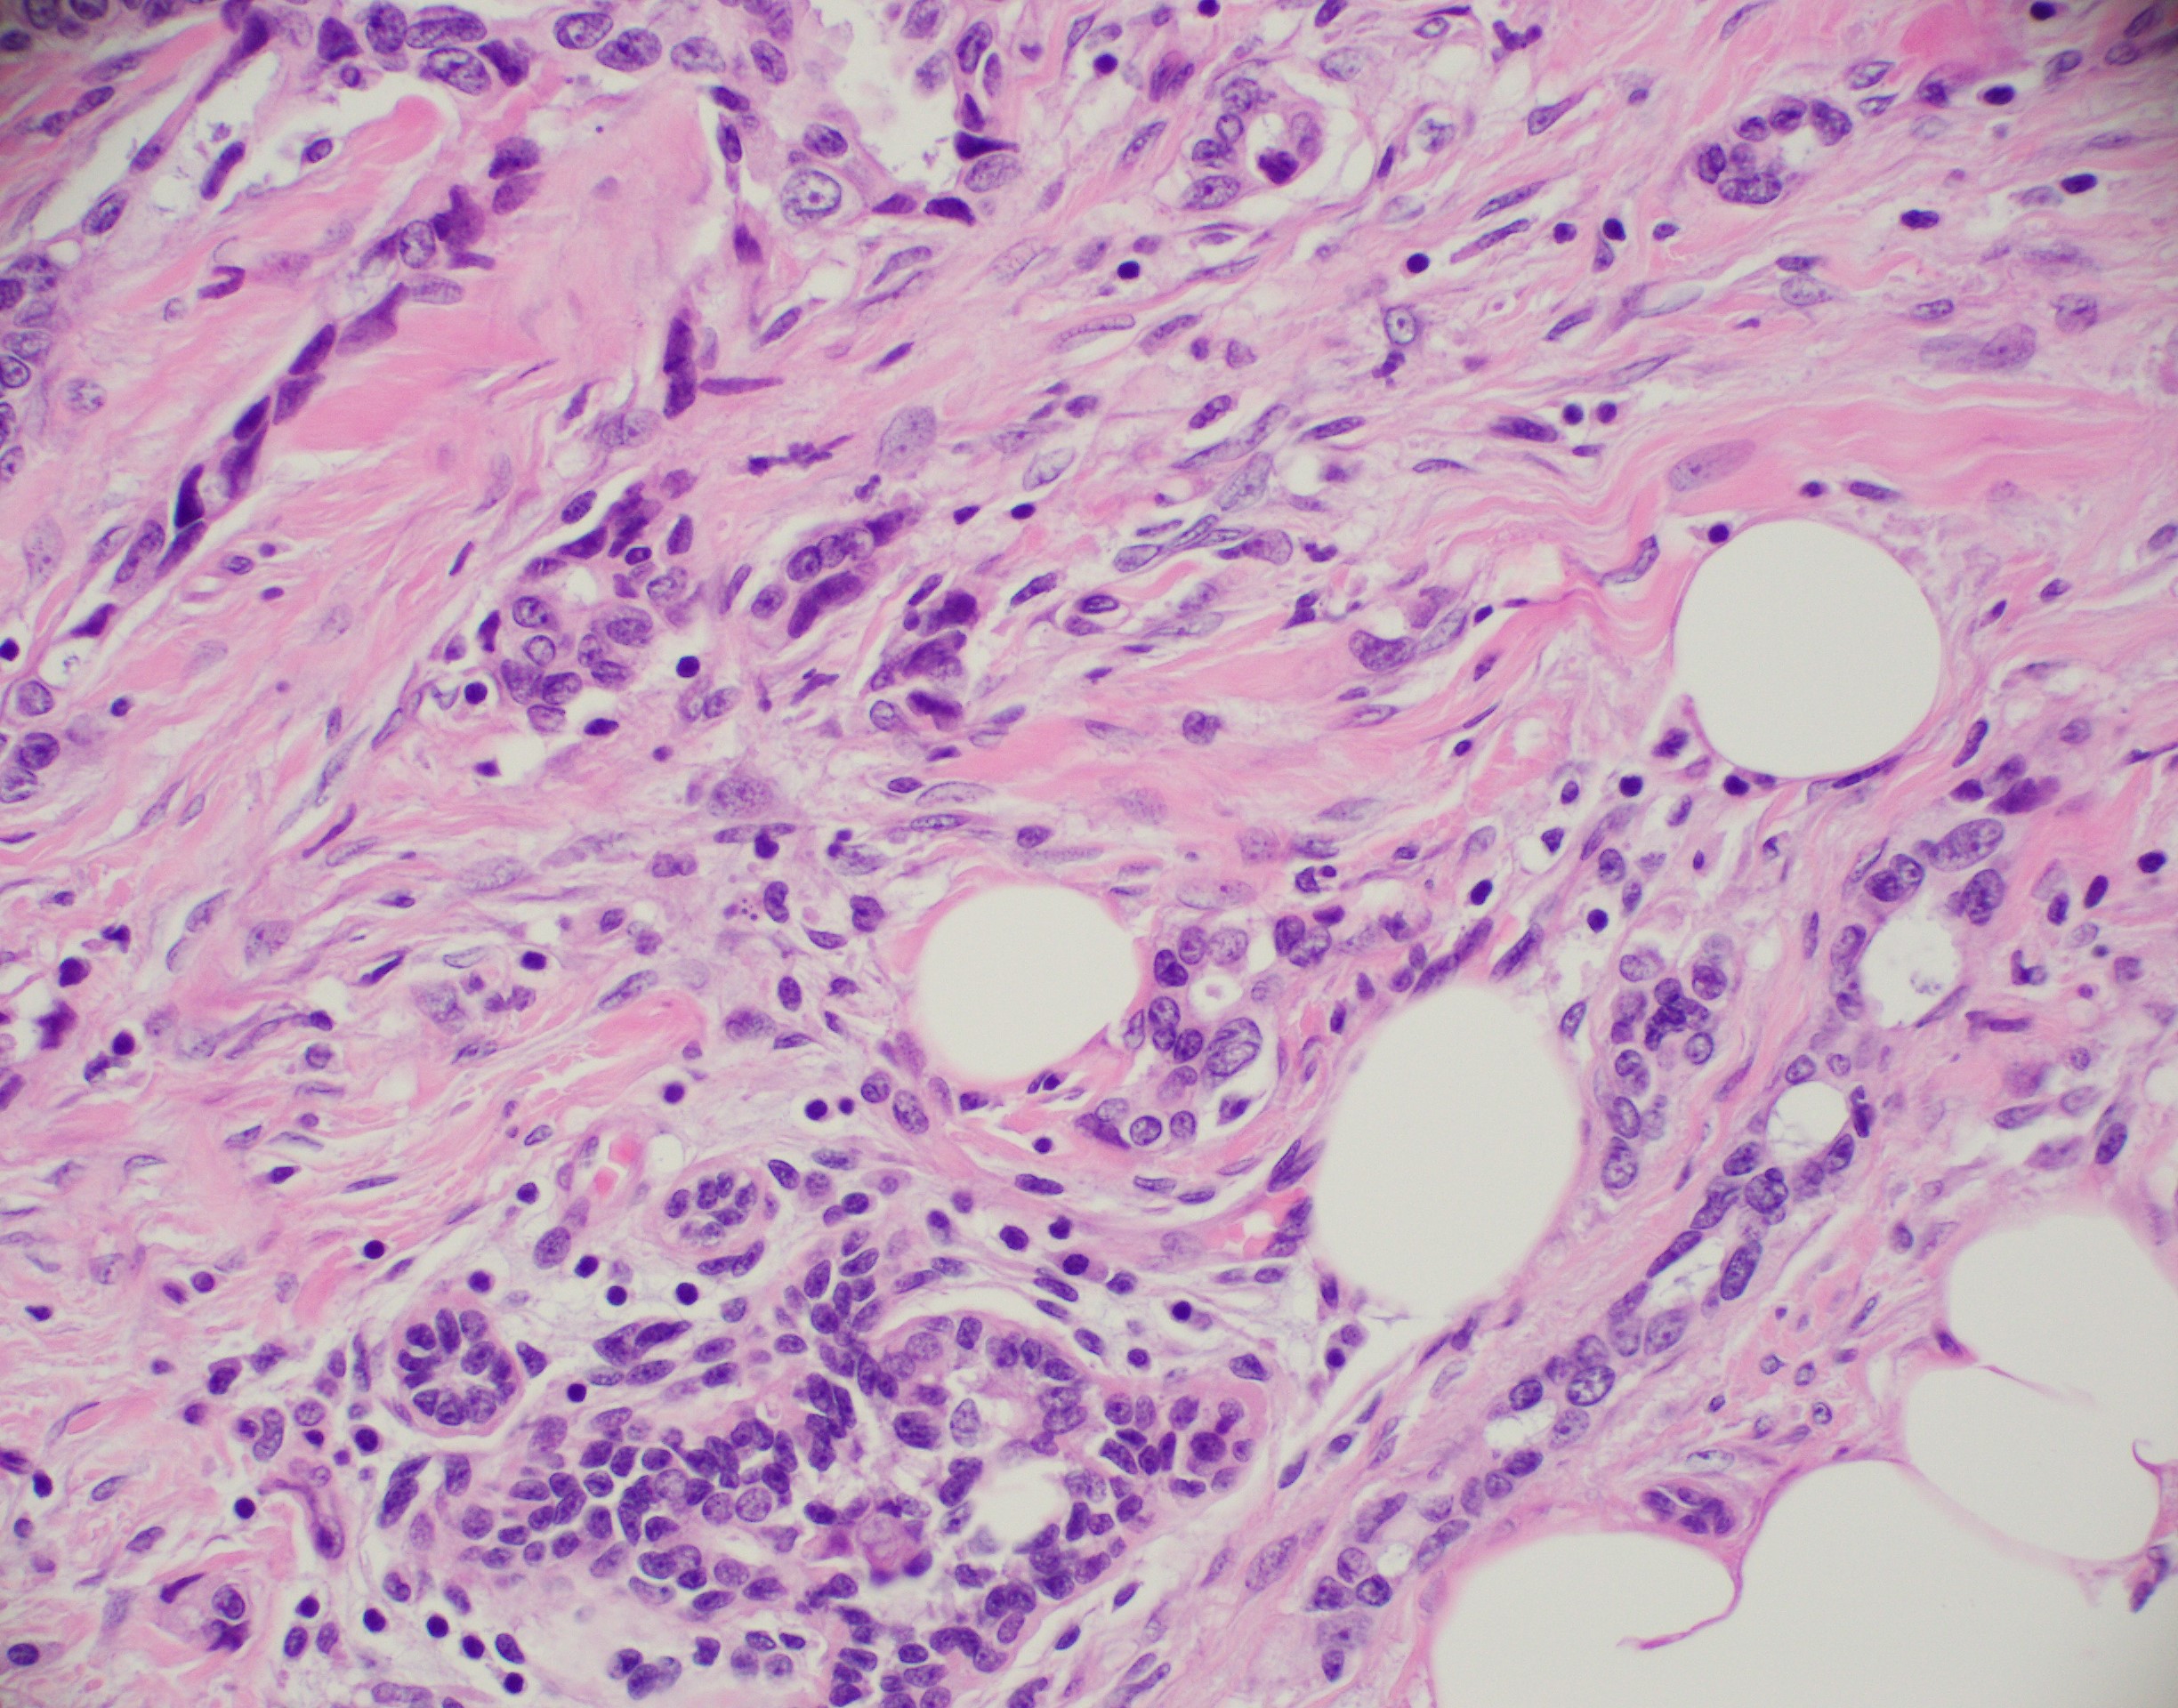

Microscopic (histologic) images

Contributed by Julie M. Jorns, M.D., Kristen E. Muller, D.O., Gary Tozbikian, M.D. and Emad Rakha, M.D.

- Variable cytological features:

- Cytoplasm may be abundant and eosinophilic but it can show other features in some tumors, including as clear, foamy or granular

- Nuclei may be regular and uniform or highly pleomorphic with prominent or multiple nucleoli

- Mitotic figures are variable from virtually absent to extensive

- Angiolymphatic invasion in 35%; differs from tissue retraction because:

- Occurs outside margin of carcinoma

- Does not conform precisely to space it is in

- Endothelial lining is present and is CD31+, ERG, D2-40+, CD34+ and factor VIII+